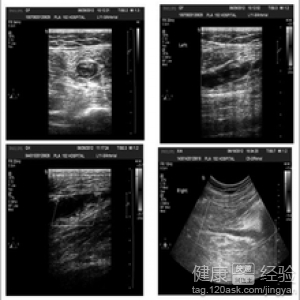

我的一個朋友是位保安,前些日他覺得自己的腿很不舒服,腿部發冷,怕冷,小腿部酸疼,尤其是走一段距離之後,就會出現小腿肌肉抽筋,需要被迫停下來,休息一段時間時候,那種疼痛就會稍微緩解,於是他就趕忙去了醫院,他的主治醫生說這是叫做間歇性跛行的一種表現,一般會有淺靜脈炎的發生,於是醫生又做了一些檢查,判斷我這位朋友得的是下肢靜脈血栓。

3主治醫生對朋友說,您現在還處於比較輕的狀況,血栓閉塞性脈管炎分為三期,局部缺血,營養障礙,以及組織壞死。一旦出現組織壞死就需要手術治療,這是很嚴重的後果,是需要截肢的,所以,平時一定要注意保護自己,做到早發病,治療,以及注意改善自己的生活習慣。

最後我的朋友出院時醫生還叮囑說,下肢靜脈血栓一般不會影響走路,但要改善自己的生活習慣,避免這種病的進一步惡化,否則,後果是很嚴重的,局部缺血期和營養障礙期都是計較容易克服的,要是一旦發展成組織壞死期,後果很嚴重,所以出院時主治醫生說,考慮該疾病,醫生建議我的這位朋友可以換一份工作,因為他現在的這份工作,一是站立時間久,二是經常容易腿累,不太利於他腿病的恢復。以上就是我的相關經驗分享,希望對您有所幫助。